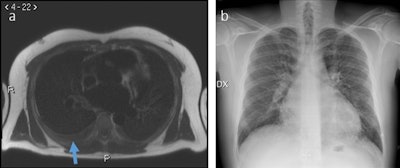

A 32-year-old man with pleural effusion visible at MRI (arrow in panel a) but not clearly visible at chest x-ray (panel b).

A 32-year-old man with pleural effusion visible at MRI (arrow in panel a) but not clearly visible at chest x-ray (panel b).Both techniques had the same detection rate for pulmonary nodule detection: 1.7%. Interreader agreement was perfect for HASTE MRI and modest for chest x-ray. The pleural effusion detection rate for HASTE MRI was higher than chest x-ray, but their agreement was almost perfect. The pulmonary infiltrate detection rate at HASTE MRI was equivalent to that at chest x-ray, with an almost perfect intertechnique agreement. The interreader agreement was moderate for both HASTE MRI and chest x-ray. Results are summarized in the table below.